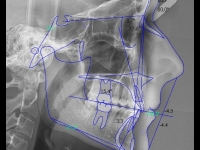

Clase II paciente 15 años

Ago

2013

2013

26

La paciente O.O. acude a nuestra consulta por:

– Canino 13 e incisivo lateral 42 en posición ectópica.

– Canino 23 incluido.

Con lo que decide realizarse un tratamiento de ortodoncia de duración de 24 meses con brackets damon Q.

CASO COMPLETO: